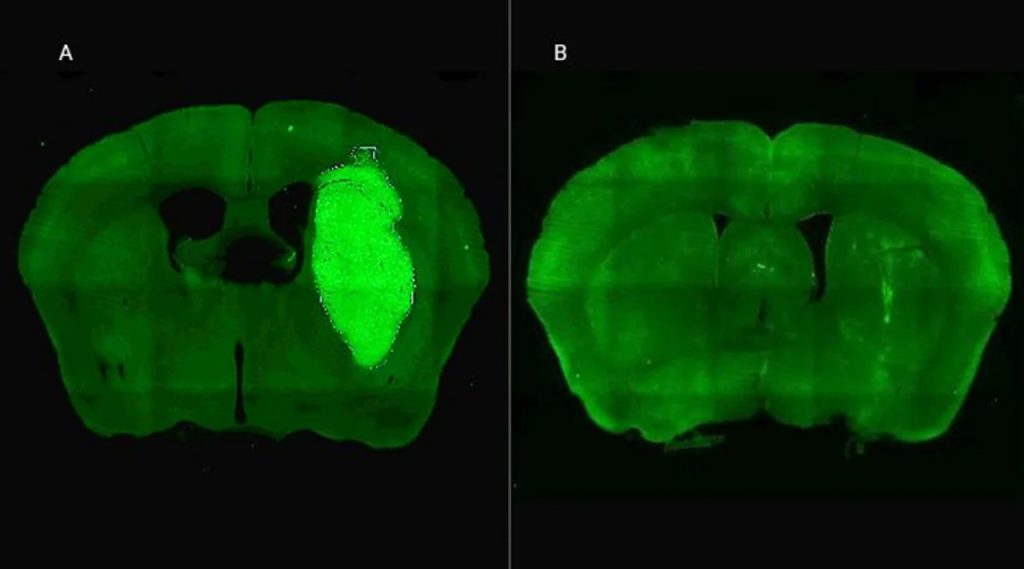

A) Se visualiza el tumor cerebral en un modelo preclínico. B) El tumor desaparece gracias a la administración de la estrategia terapéutica diseñada por los especialistas del CONICET.